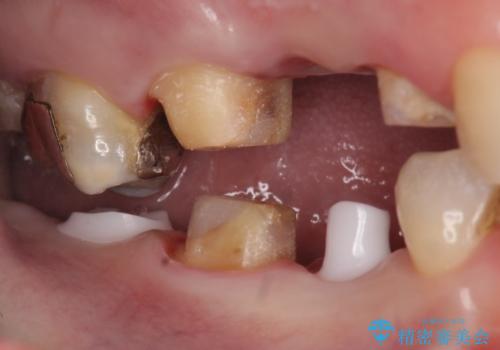

- 右下の奥歯の被せ物が外れてしまったので診て欲しいといらっしゃった方の症例です。

右下7は欠損しており、右下5は保存不可能だったため、インプラントによる欠損補綴を行いました。

インプラント埋入時には骨が不十分な部位に骨増生を行っております。